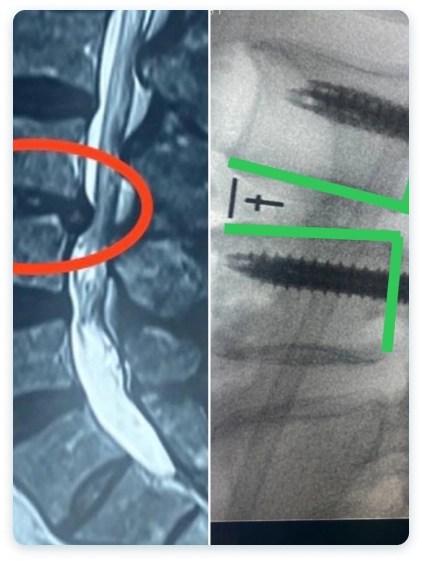

Veja casos de antes e depois dos meus pacientes:

A artroplastia lombar se concentra em preservar o movimento vertebral. Substituímos o disco intervertebral danificado por um artificial, mantendo a mobilidade vertebral.

A artrodese, também conhecida como fusão espinhal, é um procedimento cirúrgico que visa aliviar a dor. é feito a fusão de duas ou mais vértebras para estabilizar a coluna e aliviar a dor causada pelo movimento vertebral.